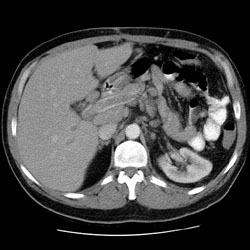

RADIOLOGY: GASTROINTESTINAL: GI: Case# 34233: 39 year old male with CLL. The patient is status post splenectomy in 8/98. The patient now presents with abdominal pain and fever.